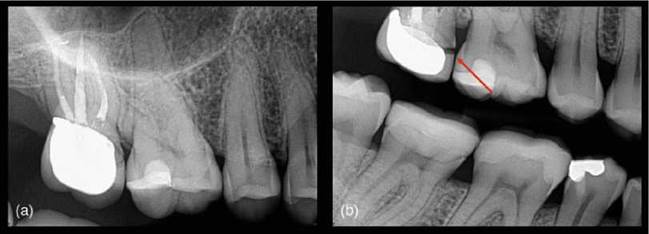

Periapical radiographs are currently the primary tool as the first line for radiographic assessment of the periapical tissues. It is a quick and simple technique to use, and images are relatively easy to interpret. In addition, it has good specificity and high image resolution. The limitations of periapical radiography are the superimposition of overlying anatomy; the 2-dimensional nature of the image being produced; and the geo- metric distortion (Figure 6.1). These factors result in less than ideal sensitivity [93].

Figure 6.1 Geometric distortion. (a) Periapical radiograph of a root treated upper right molar tooth does not reveal anything untoward, (b) however, the change in the bitewing radiograph reveals a deficient crown margin (red arrow).